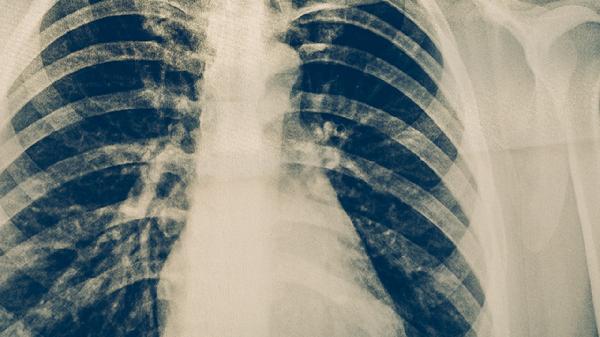

慢性肺源性心脏病急性发作的治疗方法主要有氧疗、药物治疗、机械通气、控制感染、纠正心力衰竭等。慢性肺源性心脏病急性发作通常由呼吸道感染、肺动脉高压加重等因素诱发,表现为呼吸困难加重、下肢水肿等症状。

呼吸道感染是慢性肺源性心脏病急性发作的常见诱因,需根据痰培养和药敏结果选择敏感抗生素。常用抗生素包括左氧氟沙星注射液、头孢曲松钠注射液等。控制感染有助于减轻炎症反应,改善呼吸道症状。抗生素使用需足量足疗程,避免耐药性产生。